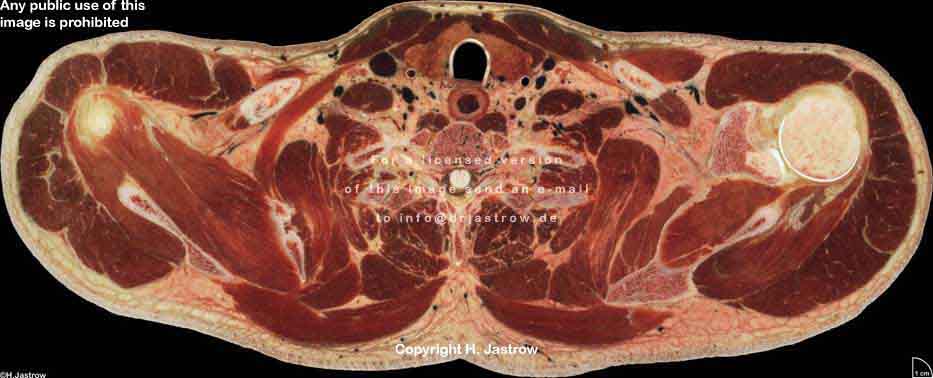

Visible Human male: Sectio transversalis 1294

CT

NMR

Pd T1 T2